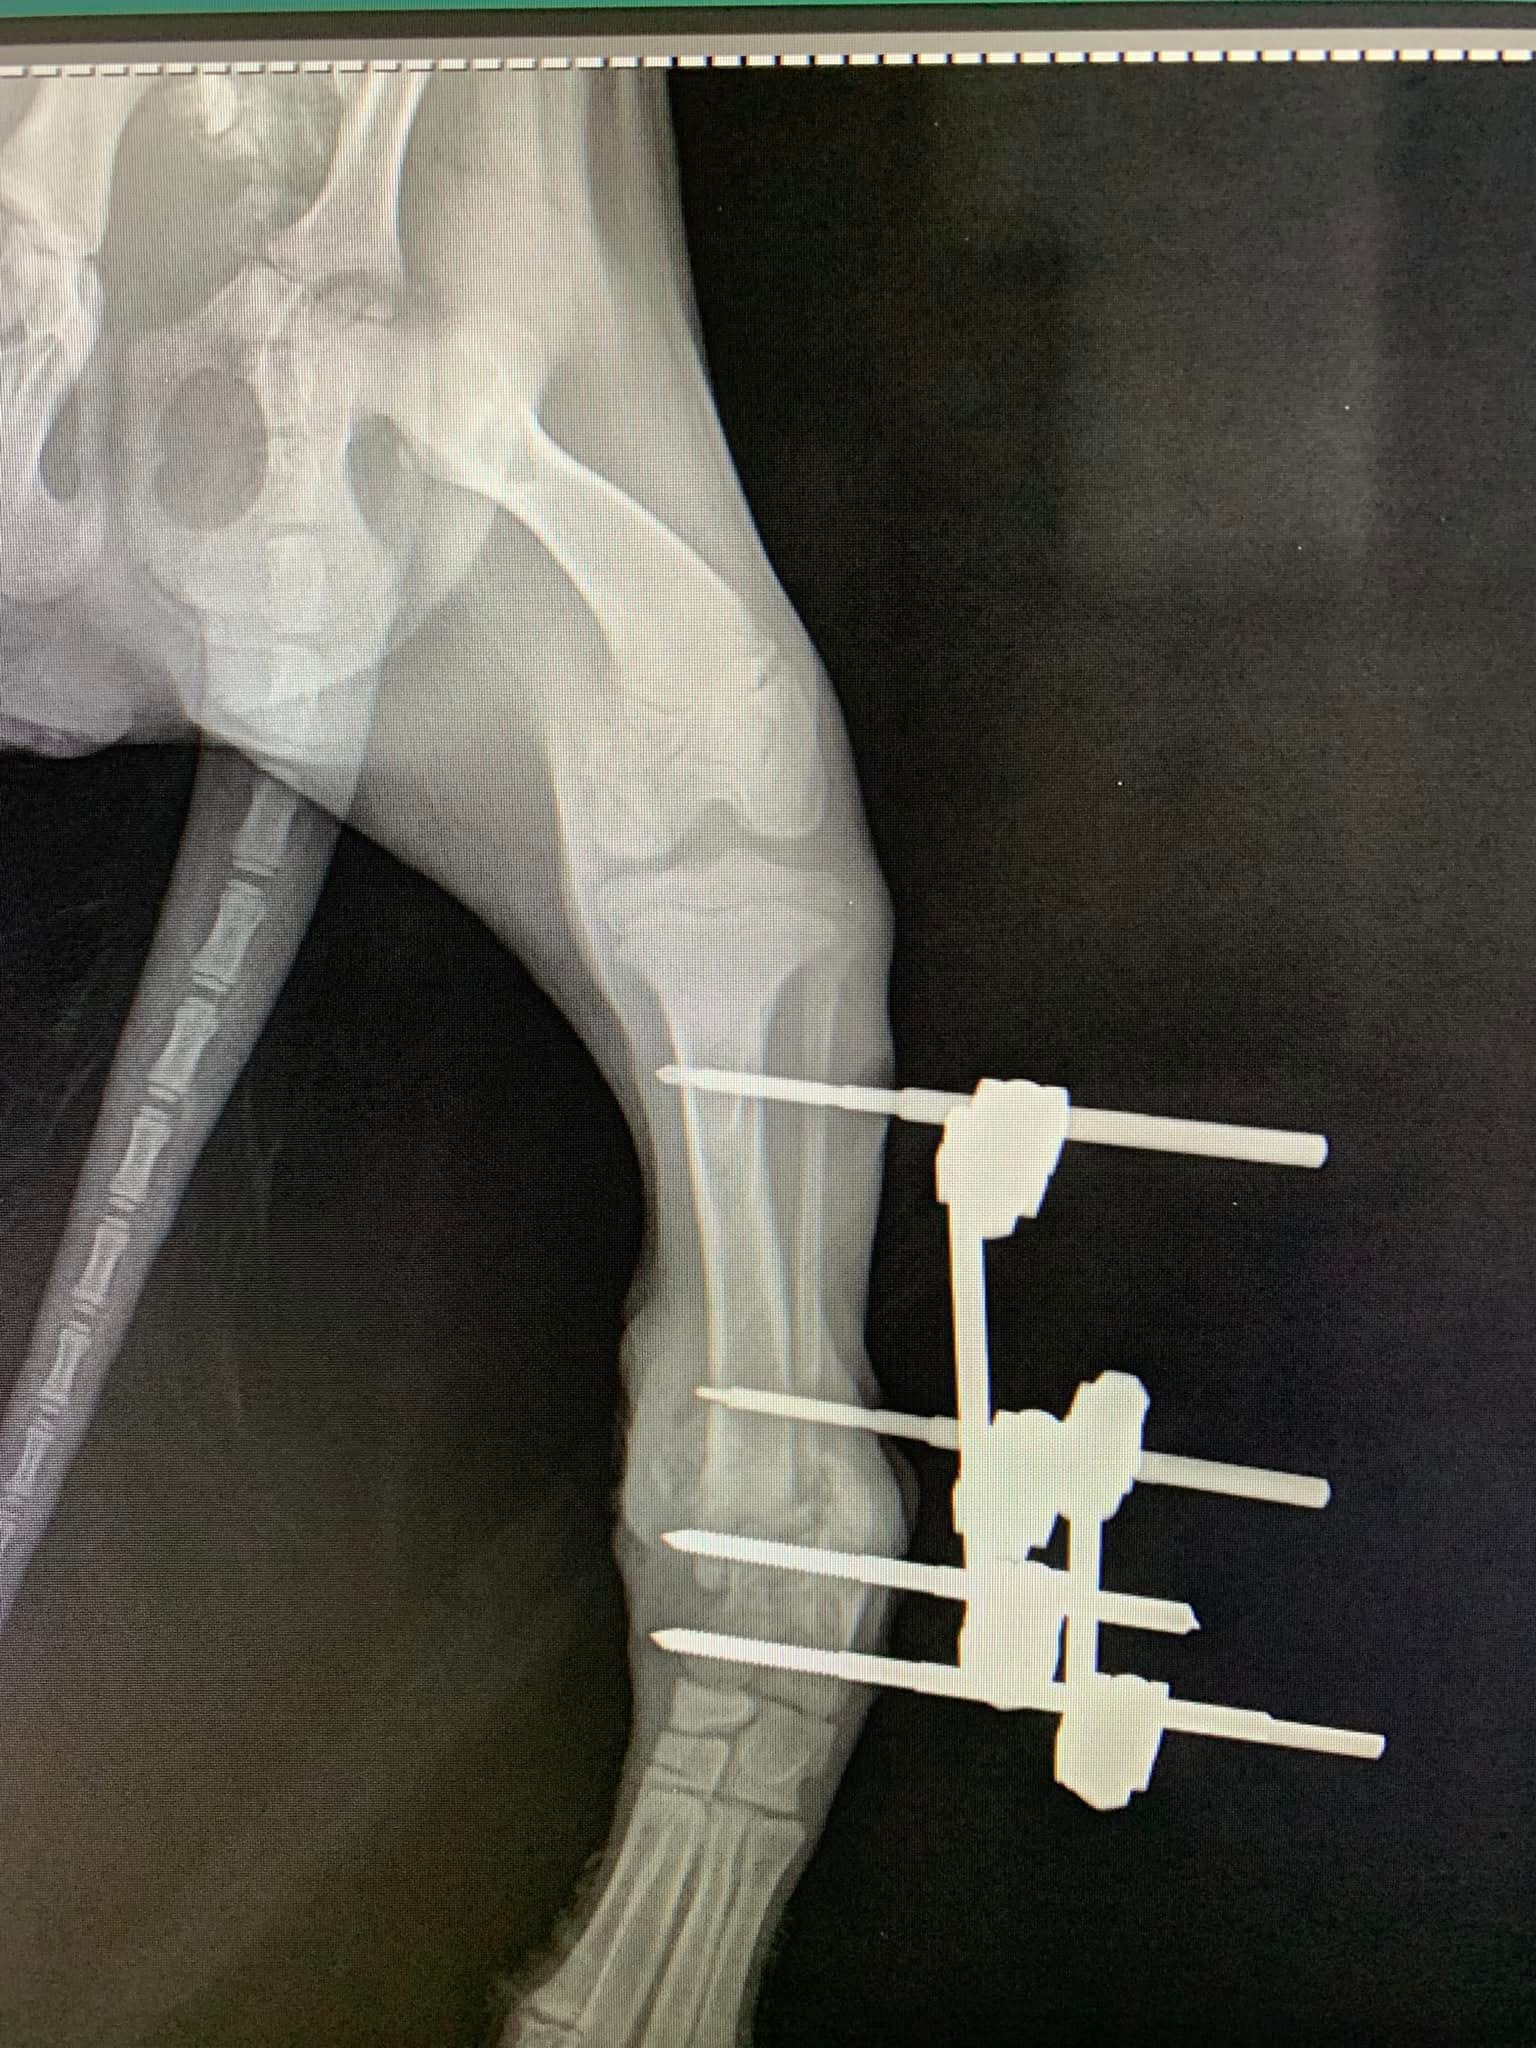

- Liječenje prijeloma kostiju, uključujući intraartikularne frakture

- Hirurške intervencije na zglobovima(artrotomija, artrodeza)

- Korektivne osteotomije za ispravljanje deformiteta